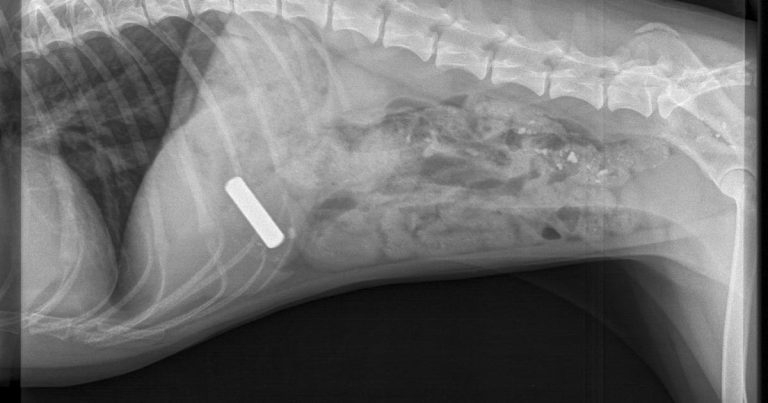

After an initial examination, x-rays showed the AAA battery in Meadow’s stomach, leading senior vet Kieran O’Halloran to act swiftly to prevent any serious damage.

“Once the x-rays confirmed the battery was in Meadow’s stomach in one piece, we induced sickness and it soon reappeared with no harm done.”